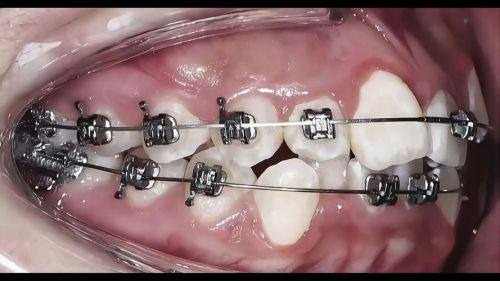

牙齿美容整形多少钱?2026年最新价格揭秘与注意事项! 本文围绕2026年牙齿美容整形价格及注意事项展开。牙齿整形费用参考范围8000 - 30000元,受畸形程度、地区、矫治器材料等因素影响。不同矫治器材料费用有别,国产亲民、进口稍贵、隐形更贵。还介绍了医院医生、治疗方案等影响价格的其他因素。同时给出选择正规机构、与医生沟通等注意事项,助大家选合适方案美牙。 牙齿美白 2026年03月04日 0 点赞 0 评论 7 浏览